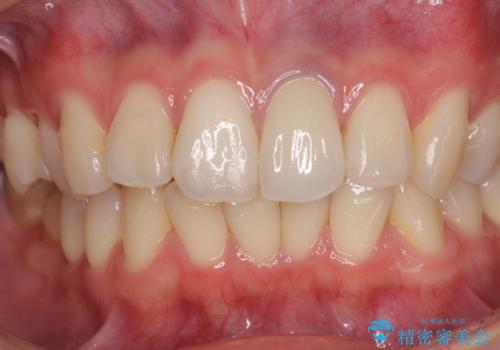

オーダーメイドタイプのクラウンを選択いただいたので、まるで天然の歯と見間違うほど自然に仕上がり、患者様には大変満足していただきました。